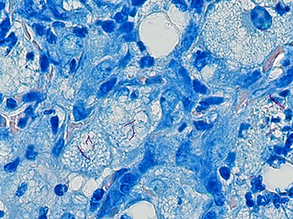

Protect Against Obesity